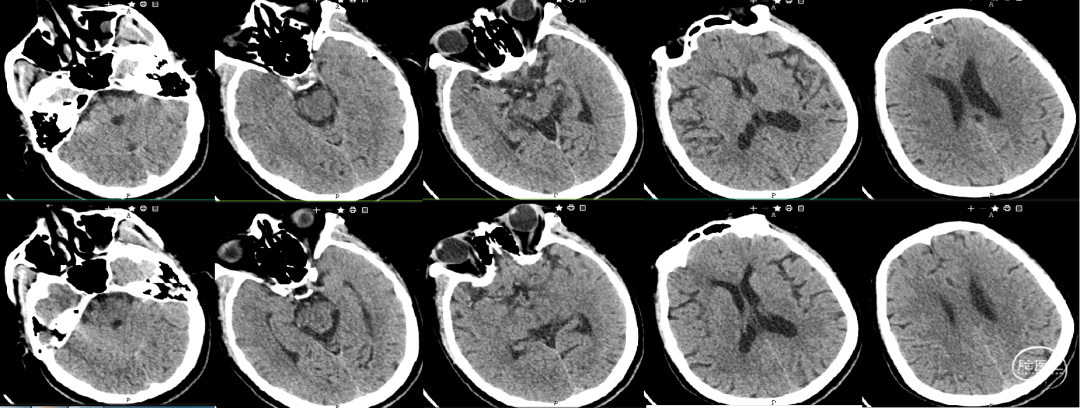

术前头颅CT影像学检查结果——排除脑出血